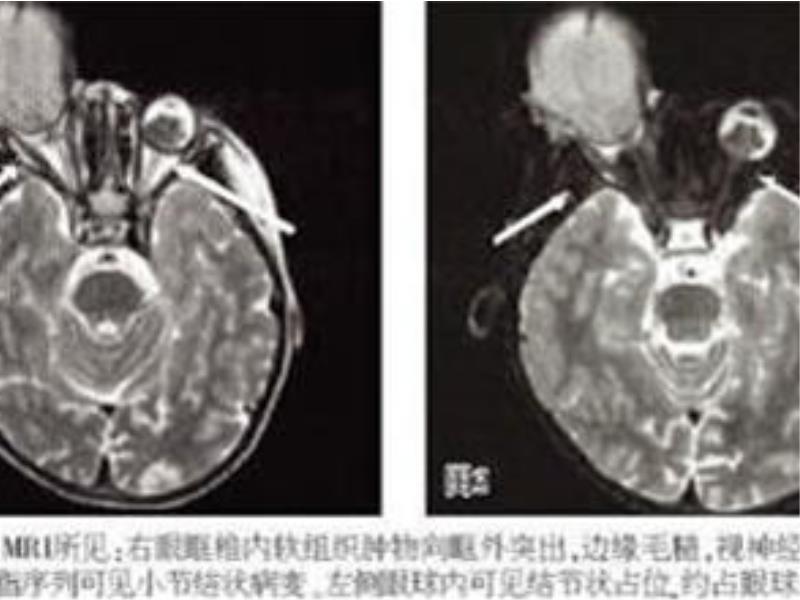

經過醫院詳細的檢查後,醫生確認寶寶是患上了視網膜母細胞瘤,並且已經到了晚期,只能是進行手術,摘除右眼球,以防癌細胞擴散。

做了右側眼球摘除手術後,寶寶慢慢身體康復,醫生還專門為他量身定做了人工眼球,和真眼球無異。

目前醫學上對視網膜母細胞瘤還沒有明確病因,常見於嬰幼兒,主要症狀是白瞳、斜視、視力下降和眼球充血等,如若發現應及時到醫院就診,切勿耽誤病情導致惡化。